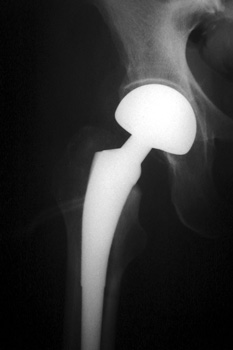

HETEROTOPIC BONE FORMATION—Early heterotopic ossification (arrows) occurring 6 weeks after surgery